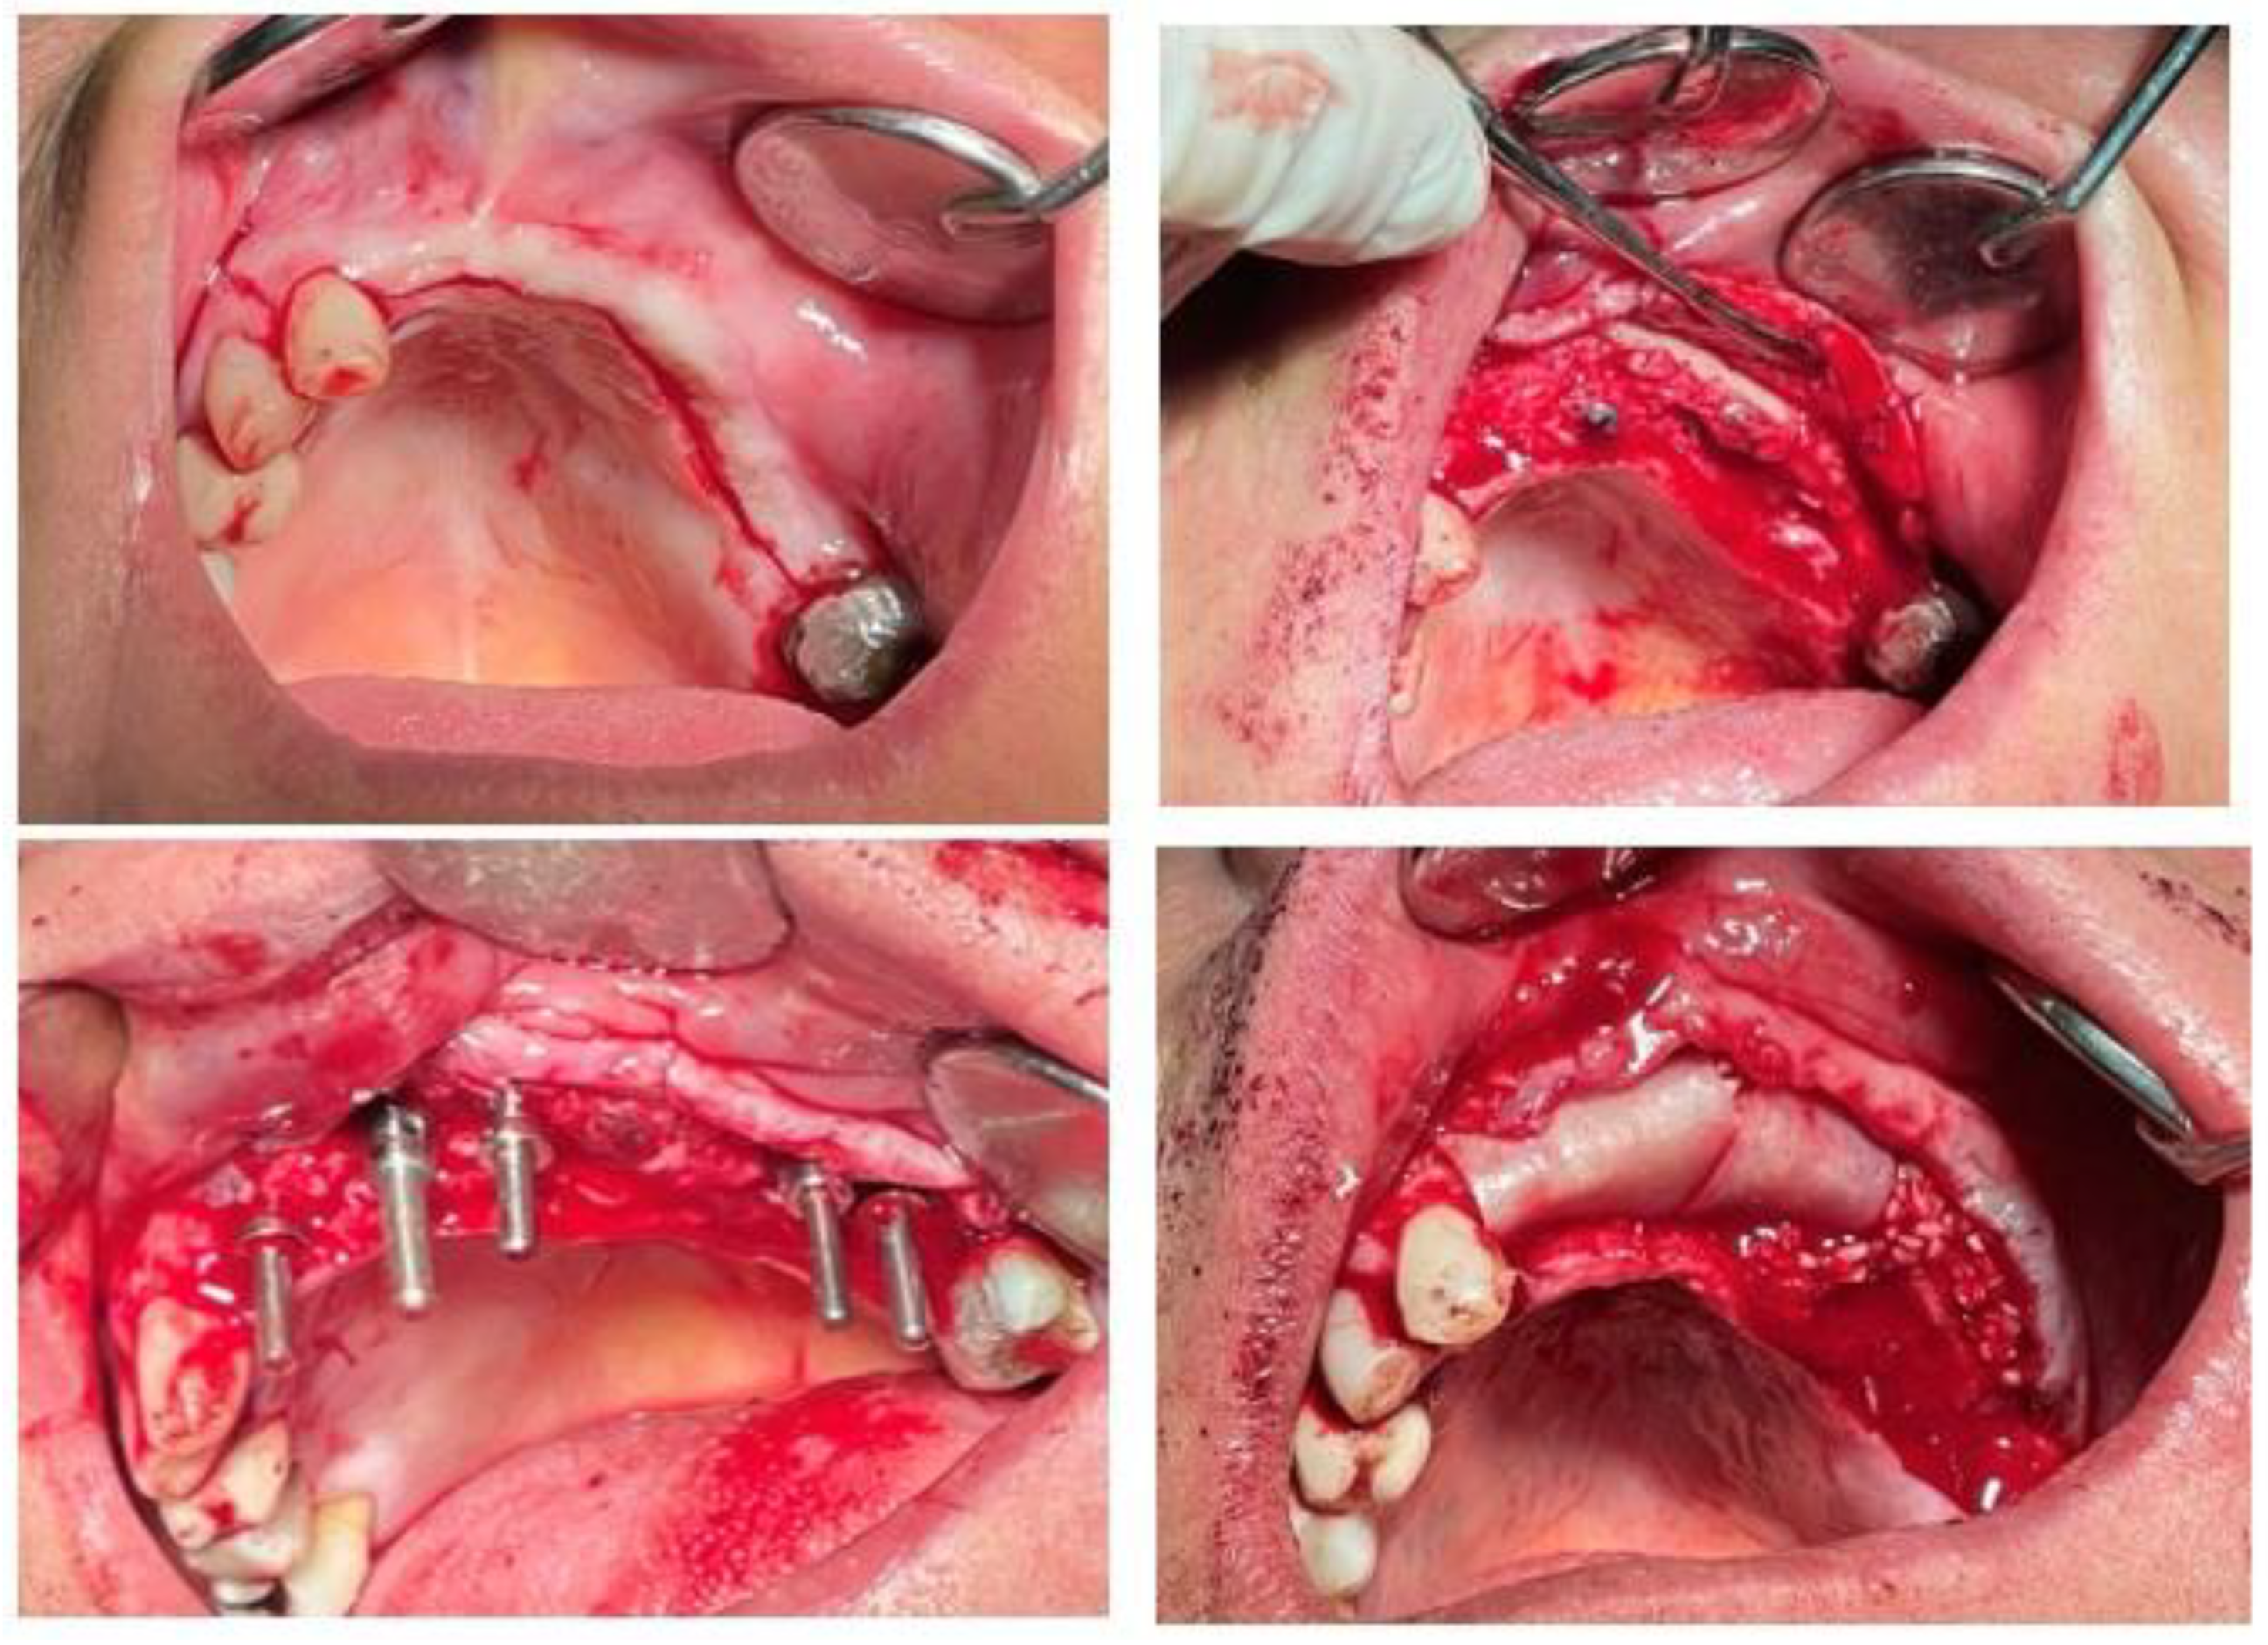

The diagnostic records, including preoperative intraoral photographs, study casts, panoramic radiographs, and CBCT scans, clearly illustrated the pronounced ridge deficiencies and the absence of keratinized mucosa in the anterior maxilla (Figure 1, Figure 2, Figure 3, Figure 4 and Figure 5).

Figure 1. Preoperative intraoral photograph showing severe horizontal and vertical ridge deficiency and lack of keratinized mucosa. Diagnostic cast illustrating the edentulous maxillary segment.

Figure 6. Intraoperative views showing: (A) placement of cortical cancellous allograft and bone plate fixation for ridge augmentation; (B) open sinus lift procedure with Schneiderian membrane elevation; (C) primary closure with direct suturing technique; (D) immediate postoperative application of low-level laser therapy (808 nm, 0.3 W, 6 J/cm²) to enhance soft tissue healing.

Figure 8. Surgical stages of implant placement: (A) crestal alveolar incision; (B, C) sequential placement of IRES Swiss dental implants at planned sites; (D) application of cortical cancellous allograft around implants to increase alveolar ridge width and enhance labial support.